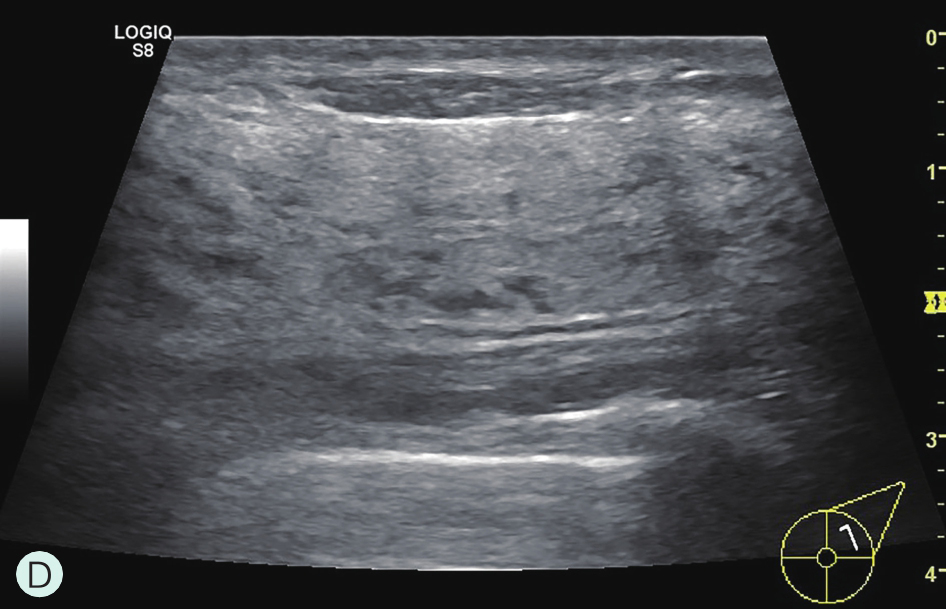

C级:不均匀致密型(可能掩盖小肿块)(图1-3-1C、图1-3-2C、图1-3-3C)。

D级:极度致密型(降低乳腺钼靶摄影的敏感性)(图1-3-1D、图1-3-2D、图1-3-3D)。

图1-3-2 乳腺超声不同乳腺密度

A.脂肪型;B.散在致密型;C.不均匀致密型;D.极度致密型